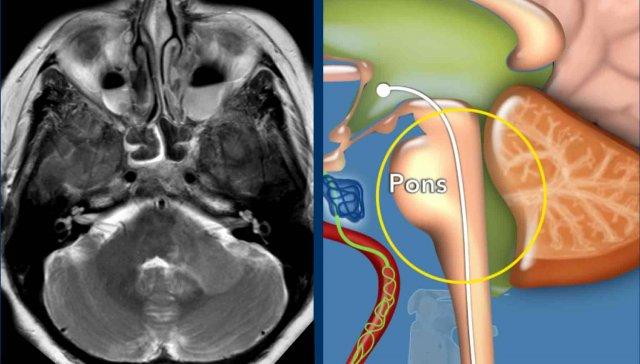

Người đàn ông 45 tuổi khởi phát đột ngột

hội chứng Horner, khó nuốt, mất điều hòa cùng bên, rung giật nhãn cầu và rối loạn cảm giác

cùng bên mặt và đối bên thân mình.

Hình ảnh

Hình ảnh khuếch tán có trọng số

DWI (B1000) và hình ảnh ADC cho thấy hạn chế khuếch tán ở hành tủy bên phải do nhồi máu hành tủy bên.

Continue with the MRA of the neck…

Hình ảnh MRA tương phản cổ (bên phải) cho thấy hẹp động mạch đốt sống phải.

Hình ảnh T1WFS cổ cho thấy tín hiệu hình liềm tăng tín hiệu trong thành động mạch đốt sống phải, điển hình của tụ máu trong thành mạch.

Kết luận

Bóc tách động mạch đốt sống phải gây nhồi máu hành tủy.